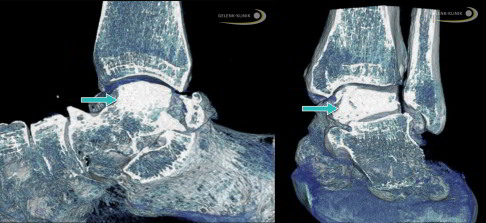

Nach einem Kollaps des Knochens unter dem Gelenkknorpel (subchondraler Knochen) kann nur das DVT (digitale Volumentomografie) die genaue Lage und Belastung der Knochenstrukturen darstellen. Das Röntgenbild als Überlagerungsbild ist ebenfalls eine gute Möglichkeit, die häufig aber – anders als die hochauflösende röntgenbasierte Schnittbilddiagnostik wie DVT oder CT – nicht die gesamte Situation der Strukturen darstellt. Daher ist ein Röntgenbild für eine Therapieentscheidung oft nicht ausreichend.

Kommt es durch die Schwächung der Tragfähigkeit und Stabilität des Knochens zu einem Zusammenbrechen (Kollaps) des nekrotischen Talus, ist eine Stabilisierung in einer guten Stellung mit Versteifung unter Einsatz von Ersatzknochen und Knochenspänen hilfreich und unumgänglich. Dies verhindert schwere Deformitäten des Fußes und eine Störung der Bewegungsabläufe beim Abrollen des Fußes.